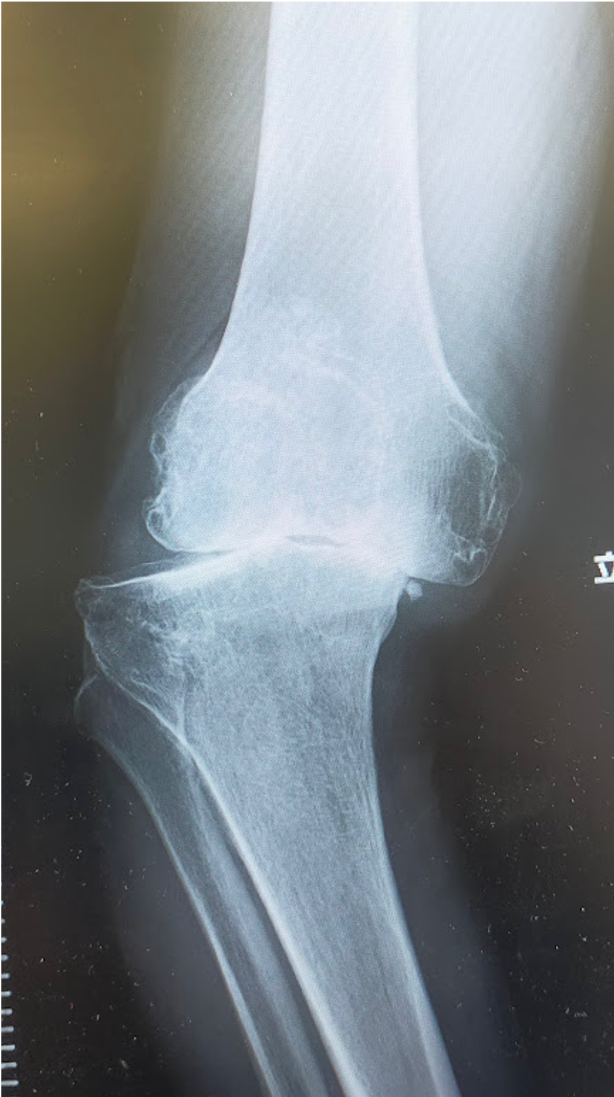

変形性膝関節症は一次性と原因疾患に続発する二次性に分類されます。わが国では年齢による退行性変化を主因とする一次性が多く、軟骨のすり減り、骨棘(骨のとげ)を伴い、多くは内反変形(O脚)を呈します。女性に多く、特に肥満との関連が強いといわれています。膝関節には歩行するだけで体重の3倍の力がかかるといわれており、病状の予防や進行を抑えるためには体重のコントロールが最も重要です。症状には波がありますが、次第に進行し、変形も悪化してきます。まずは保存加療を行いますが、痛みが強く日常生活に支障をきたすようだと、我慢するメリットはありません。痛みのない脚でより良い人生を送るために手術という選択肢もありますので、痛みで悩まれている場合は早めにご相談ください。

大腿骨顆部は体重を支えるのに重要で、過度なストレスが加わり壊死に陥ることがあります。原因としてステロイド投与や半月板損傷後などに脆弱性骨折(軽微な外傷により軟骨下骨に微小骨折を生じる)が起こり壊死に至るとされています。安静にしていても痛みが出たり、夜間寝ている間に痛みが出ることもあります。

当院にて両側の人工ひざ関節全置換術(TKA)を施行。

高度のO脚変形があり、歩行時のひざの不安定感も強い症例です。

キネマティックアライメント法で手術を行いました。

キネマティックアライメントとは、ひざ本来の靭帯のバランス、下肢の形を取り戻すことに重点を置いた方法です。

〈手術前のレントゲン〉

〈手術後のレントゲン〉